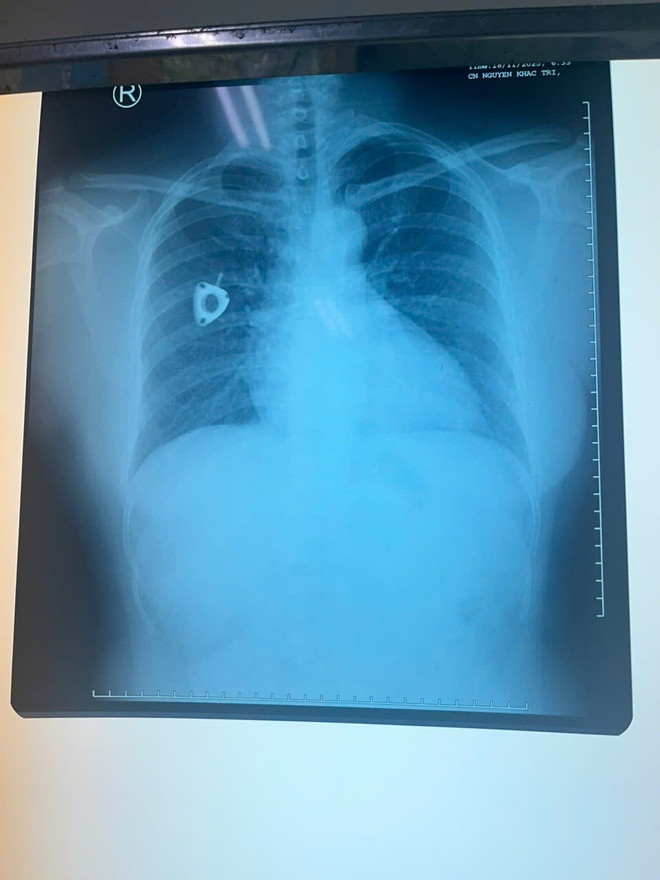

Ê-kíp phẫu thuật và dị vật được lấy ra

Ê-kíp đã lựa chọn phương pháp lấy dị vật qua đường tĩnh mạch đùi, tránh phẫu thuật mở ngực – mổ tim vốn tiềm ẩn nhiều rủi ro và thời gian hồi phục kéo dài. Dụng cụ snare chuyên dụng được đưa từ tĩnh mạch đùi lên tĩnh mạch chủ dưới, vào nhĩ phải, qua van ba lá đến thất phải và tiếp cận động mạch phổi. Tại vị trí phân nhánh động mạch phổi, một điểm rất khó tiếp cận, ê-kíp đã gắp chính xác đoạn catheter bị đứt và đưa ra ngoài an toàn.